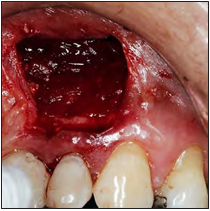

Después de la asepsia y antisepsia de la zona quirúrgica, se procedió con el bloqueo del nervio alveolar superior anterior y nervio nasopalatino (lidocaína 2% con epinefrina 1:80 000 Xylestesin, 3M ESPE, GERMANY), se realizó una incisión paramarginal con una hoja de bisturí #15 y posterior elevación del colgajo de espesor total. Ya expuesta la raíz (Fig. 2), se realizó la enucleación de la lesión, limpieza del campo quirúrgico mediante una fresa redonda de carburo tungsteno y rectificación del corte apical corrigiendo el bisel anterior por un bisel de 0° (Fig. 3). Con una gasa estéril impregnada de anestésico con vaso constrictor, se aplicó para el control de la hemorragia.

Figura 2. Primera exposición del área periapical.